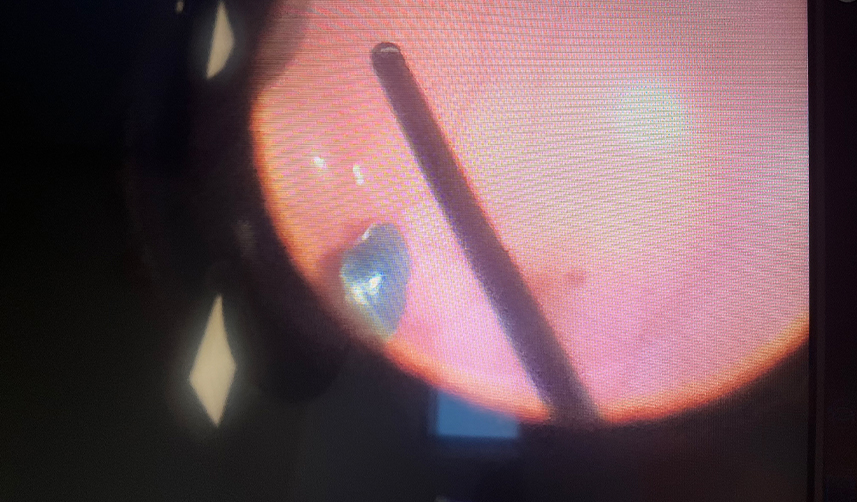

Hastanın durumu ve gerçekleştirilen operasyona yönelik konuşan Başakşehir Çam ve Sakura Şehir Hastanesi Göz Kliniği İdari Sorumlusu Doç. Dr. Altan Özal, “Hastamız Rize’den geldi, bize acil olarak başvurdu. Rize’de evinde çalışırken, tadilat işleri yaparken göz içerisine bir yabancı cismin gelmesi neticesinde ani görme kaybıyla bize müracaat etti. Çok ciddi bir göz yaralanması mevcuttu. Hemen müdahale edilmezse gözünü kaybetme riskiyle karşı karşıyaydı. Hastanın kornea, iris tabaklarında yabancı cisme bağlı bir zedelenme mevcuttu, keskin bir yabancı cisimdi. Biz kornea, iris tabalarını onardık. Aynı anda göz içerisindeki yabancı cismi de çıkarma işlemi için vitreoretinal cerrahi operasyonunu gerçekleştirdik. Göz içinde kanama ve retinada ciddi yırtıkları vardı. Bundan dolayı vitreoretinal cerrahi işlemi yapmamız çok elzemdi, bu işlemleri aynı anda gerçekleştirdik. Göz içerisindeki yabancı cismi çıkararak diğer dokuları onararak hastanın görmesine kavuşmasını sağladık” ifadelerini kullandı.

Tadilat işlemleri yaparken kullanılacak koruyucu malzemelerin büyük hasarların önüne geçtiğine vurgu yapan Doç. Dr. Altan Özal, “Hastanın göz içerisindeki yırtıkları olduğu için beraberinde bir tamponat madde de koyduk. Bundan dolayı hasta şu anda göz içerisinde gaz olduğu için bir süre göremeyecek ama yaklaşık 1 ay içinde görmesine kavuşacak. Tabi ki de önlem çok önemli ev ve iş kazalarında çok sıklıkla görebiliyoruz. Bu tarz tadilat işleri yapılırken ya da işyerlerinde çalışırken muhakkak koruyucu gözlük kullanmalarını öneriyoruz. Basit bir koruyucu gözlükle hiç bunlara gerek kalmadan hastalarımız bu işlemleri rahatlıkla gerçekleştirebiliyorlar. Bunlar anında ve yeterli imkanlarla müdahale edilmezse gözün tamamının kaybıyla sonuçlanan ciddi rahatsızlıklara neden oluyor. Hastanın medikal tedavisini de planladık evde ilaçlarına devam edecek. Özellikle erken dönemde enfeksiyon riskinden dolayı dış ortama maruziyeti biraz azaltması gerekiyor” dedi.